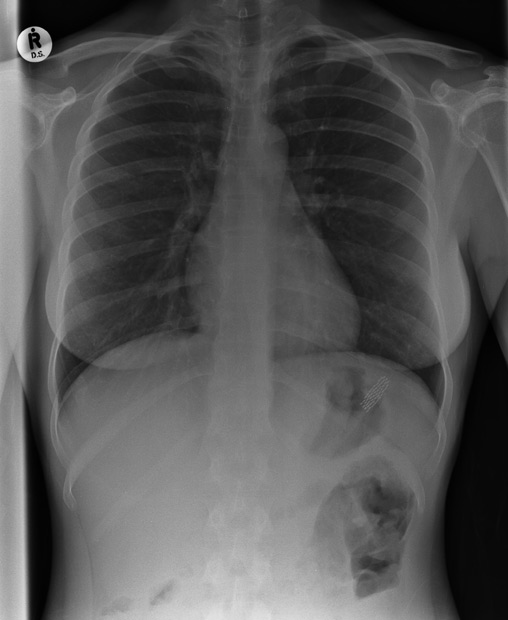

胸部X光显示链锯已经深深嵌进詹姆士 瓦伦汀(James Valentine)的颈部和肩部。据悉,美国宾夕法尼亚州匹斯堡市21岁的詹姆士当时正在树上修剪树木,突然他的链锯反弹回来戳入了他的身体。他的工友把他立即送往当地医院。